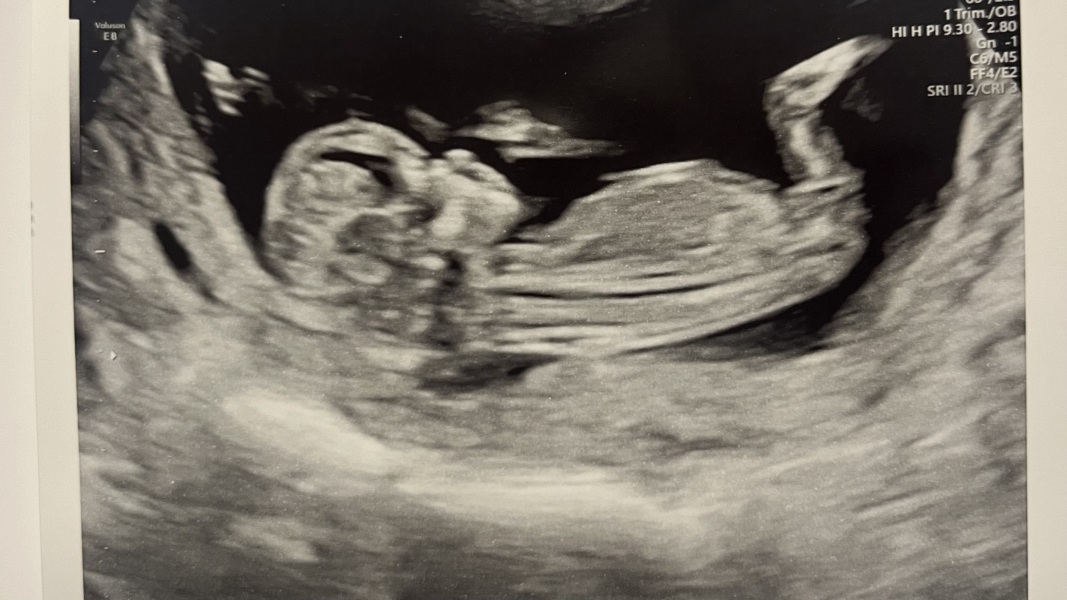

Holl89 · 28/03/2024 12:06

Hi everyone!

I was absolutely petrified but everything is looking so good 🥺❤️. Measuring ahead at 12 weeks 4 days 🩷🩵

thank you for the well wishes! xxx

Amazing @Holl89 ! What a gorgeous bub

Brilliant news @Holl89 must feel such a relief

@Holl89 oh that's lovely news! So happy for you 🥰

Awww that's a great picture @Holl89 🥰 Our due dates are quite similar so we can give each their virtual hand holds through any ups and downs (and no doubt anxious wobbles!) over the next few months 🙏☺️

So glad the scans went well!

what a gorgeous pic.